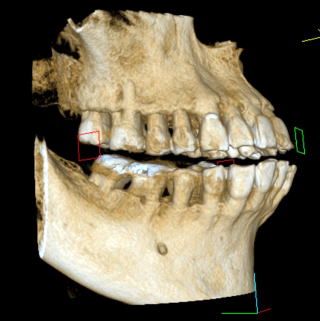

■Volume Rendering(CT)

当Clinicでは、すべてInterdisciplinary Treatment(包括的治療)を基本にしている。患者は38年間当Clinicで口腔管理をしている症例

である。開業当初から当診療システムで38年間口腔管理をしている。Panorama、CTなどレントゲンを介しての顎骨・歯槽骨の形態・骨

量などを観察したもので、歯槽骨の吸収状態から診ても、ほぼ二十歳代に相当するように思われる。過去の論文を見ても、口腔内写真

歯周病治療38年経過:83歳(女性)残存歯数28本